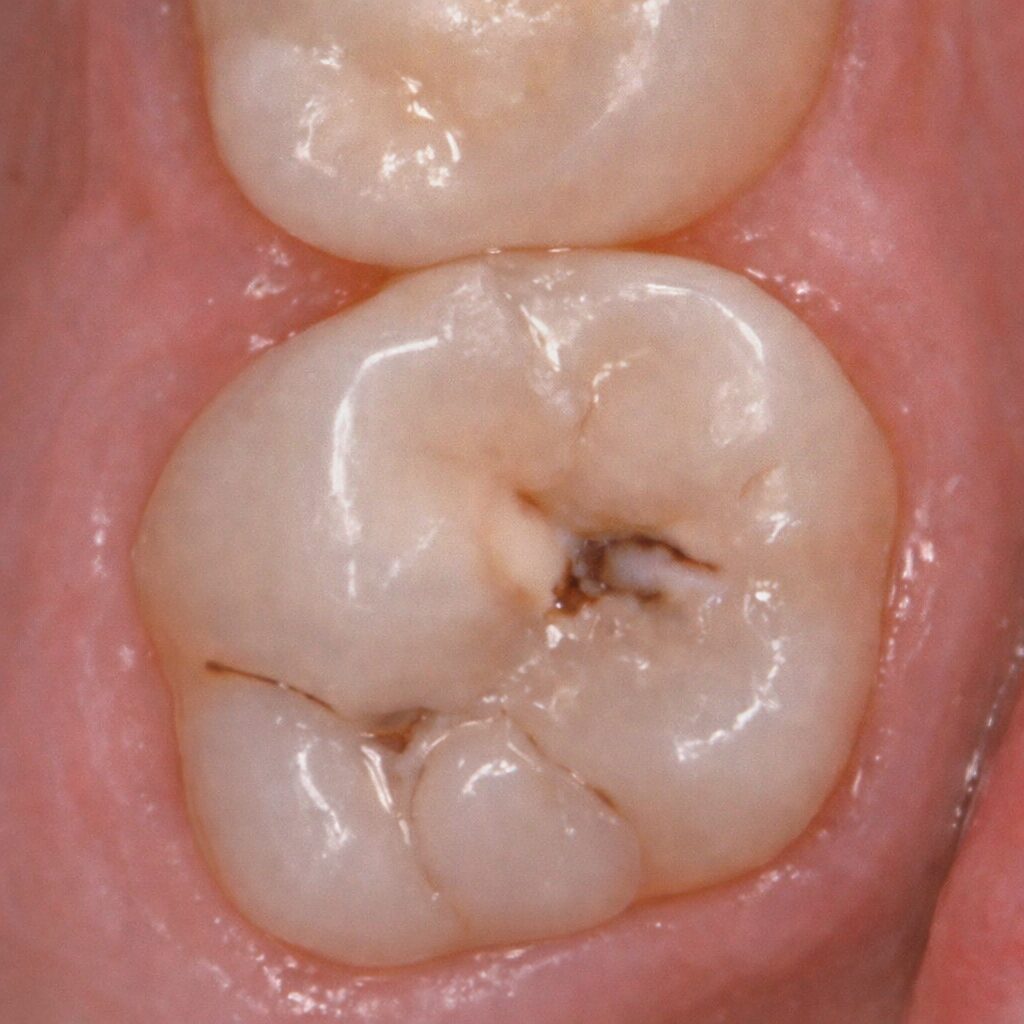

Sealant can be seen on both occlusal grooves and up towards cuspal inclines, indicating excess during placement. Sealant margins are no longer smooth, with a dark rim of shadowing seen in certain areas, and others with areas of sealant apparently chipped off.